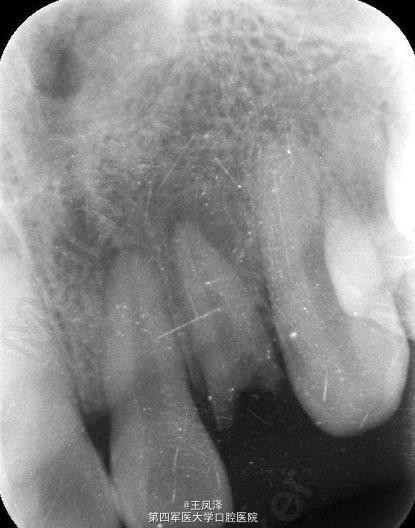

x线检查:22根尖区有阴影。诊断:22牙根纵折伴根尖周炎。

22牙根纵折伴根尖周炎。 治疗计划:1.拔除22. 2.三个月后延期种植22